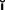

Amalgam cores are suitable for restoring posterior teeth, particularly when some coronal structure remains. The procedure described by Nayyar and associates,45 with amalgam also used for the posts, is conservative of tooth structure. The cores are placed during the same appointment as the root canal obturation, because then the teeth are still isolated by the rubber dam, the practitioner is still familiar with the root canal structure, and the cores can serve as a support for the interim restoration (Fig. 12-38).

Fig. 12-38 A to E, Retention for an amalgam core can be obtained from the root canal system, preserving as much tooth structure as possible.

(B to D, Courtesy Dr. M. Padilla.)